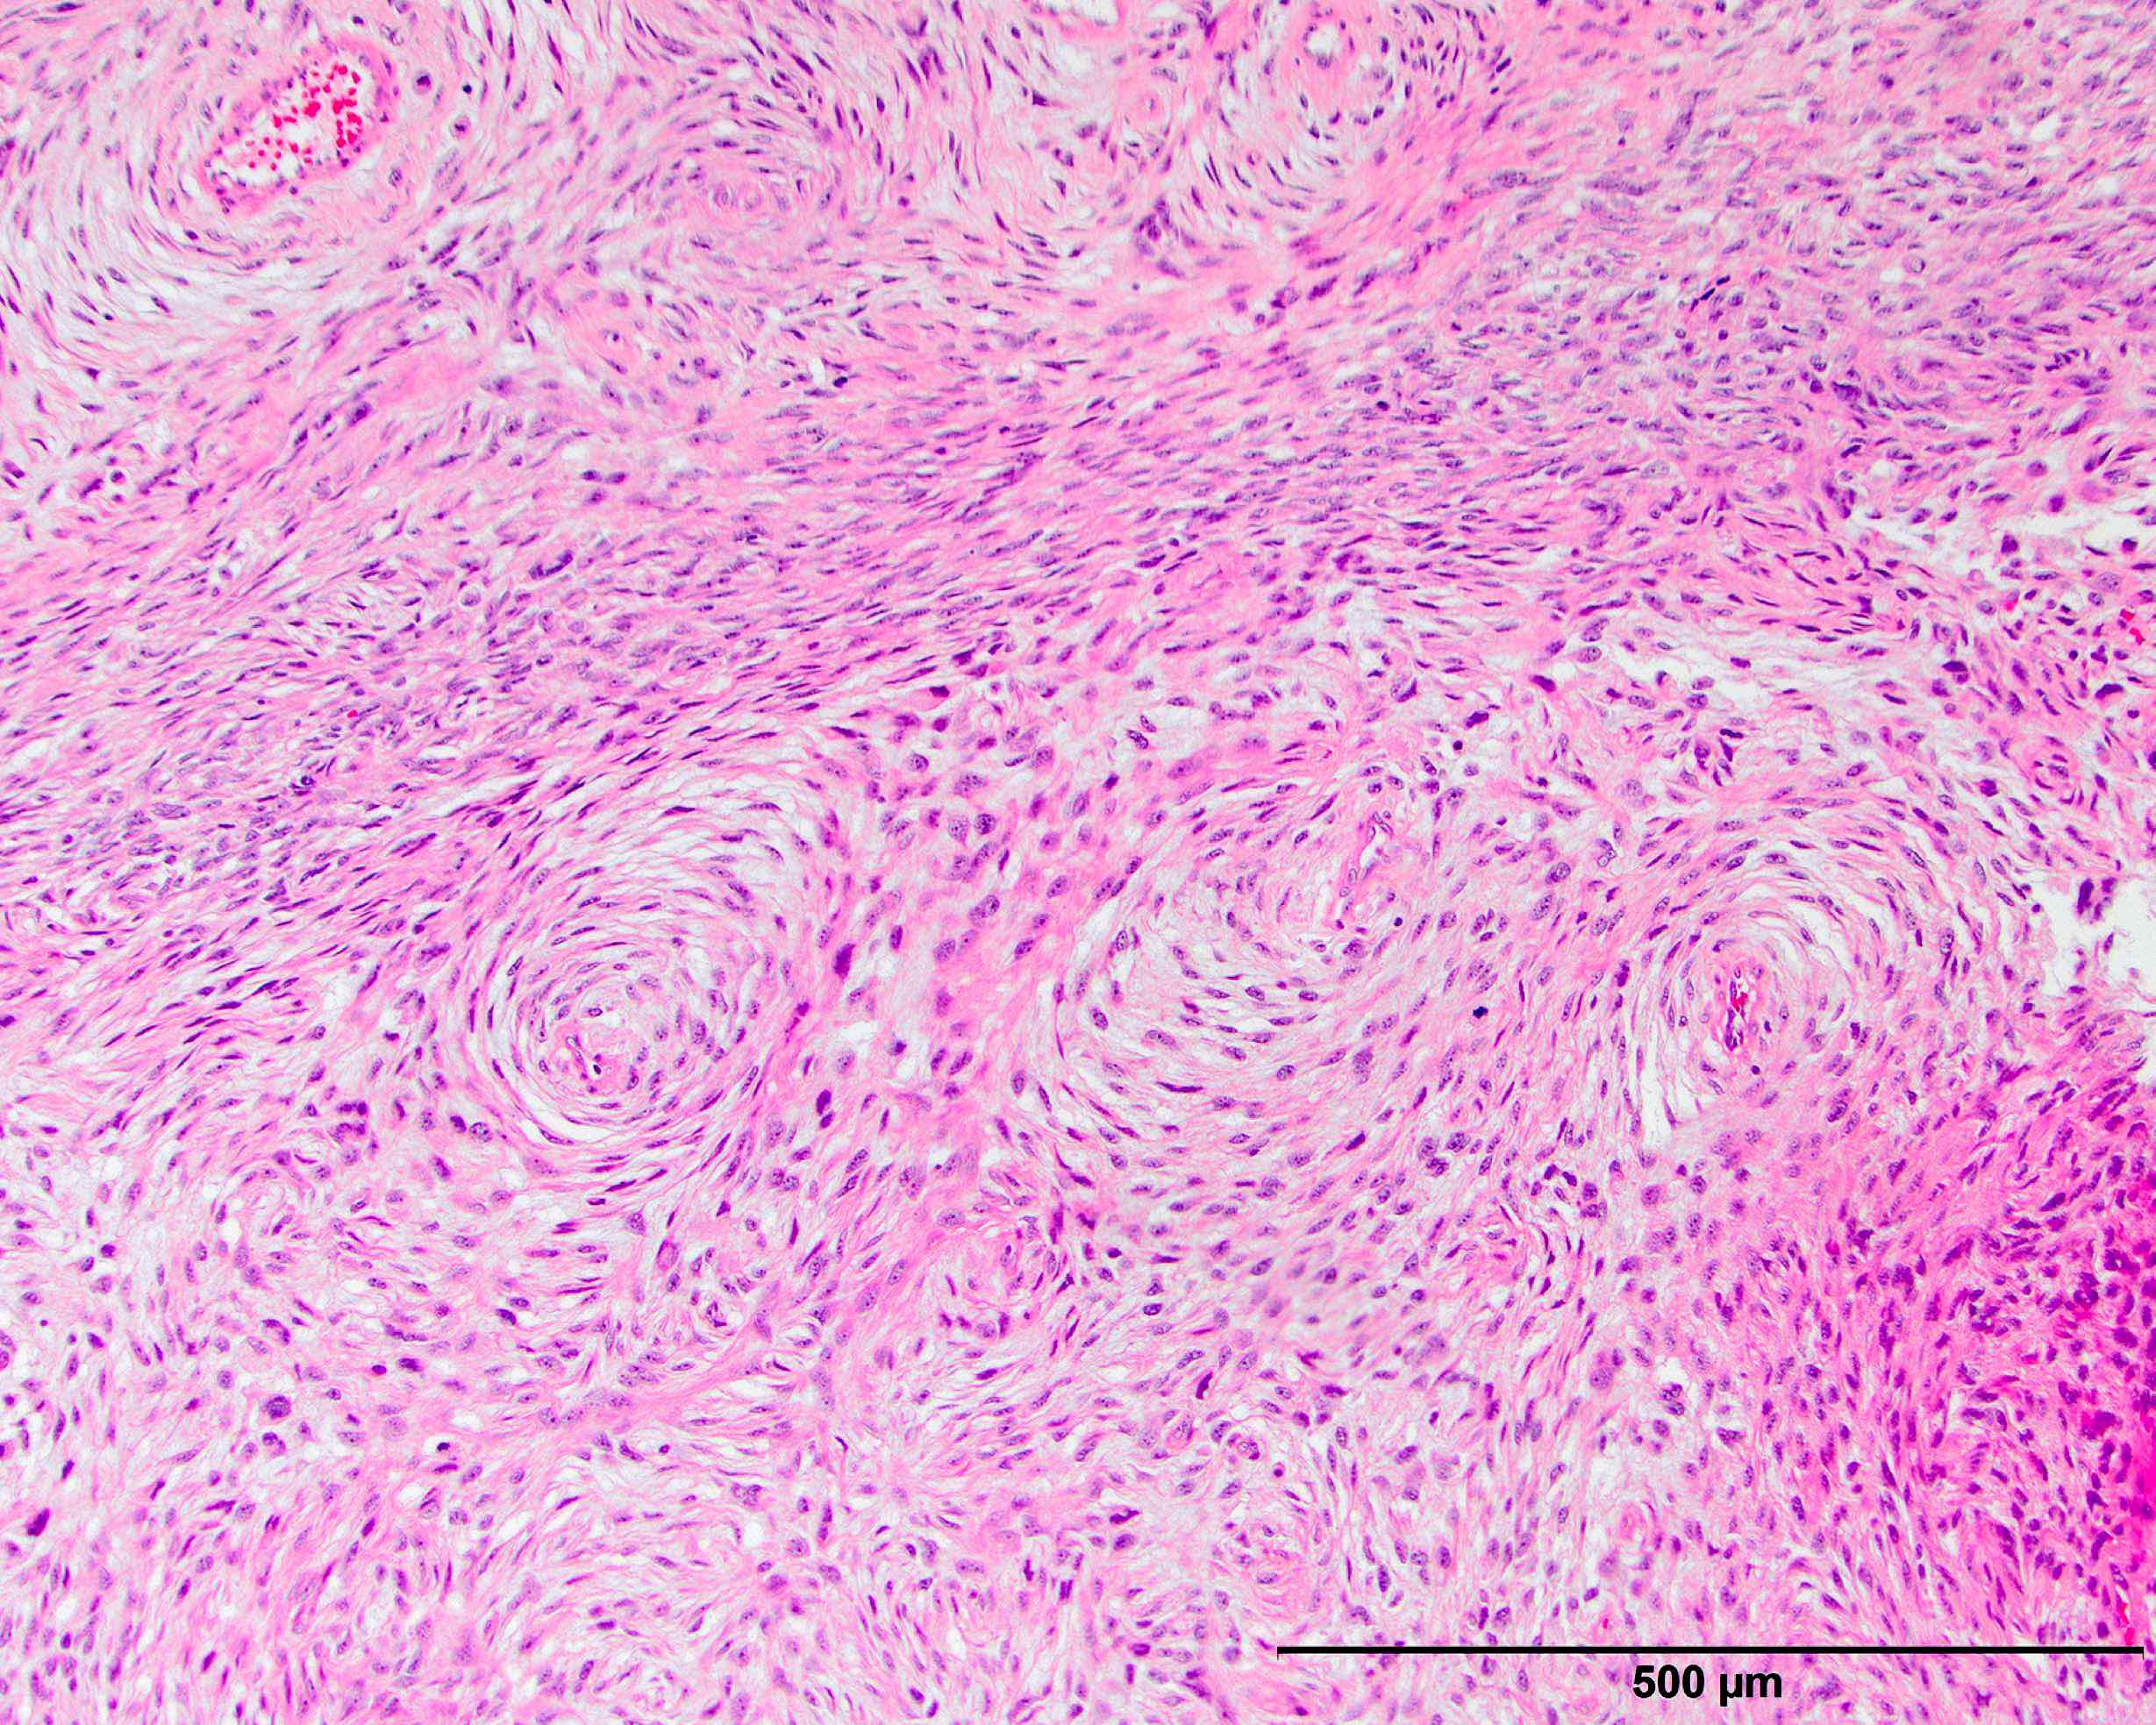

- Often resembles malignant fibrous histiocytoma (MFH), now referred to as undifferentiated pleomorphic sarcoma (UPS), with short fascicles of pleomorphic spindle cells associated with mixed inflammatory infiltrate

- Can show a peculiar whirling pattern reminiscent of meningothelial structures (Histopathology 1998;33:414, Am J Surg Pathol 1998;22:945)

- Low grade dedifferentiated liposarcoma

- Less common low grade tumor resembling fibromatosis or well differentiated fibrosarcoma

- Nonlipogenic (in contrast to well differentiated spindle cell liposarcoma, which contains atypical fat / lipoblasts)

Microscopic (histologic) images

Contributed by Michael R. Clay, M.D. and AFIP